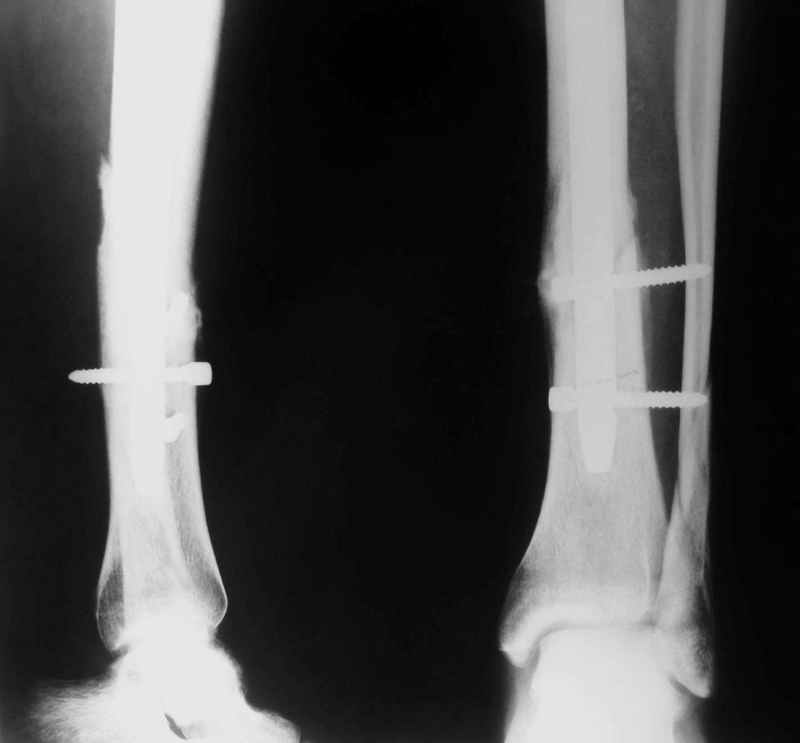

Не удается отправить первичные снимки. А что скажите по имеющимся?!

Выполненный остосинтез нестабилен. Штифт надо заменить по "размеру" на солидный, дистльно три запирающих винта. Успехов!

Перелом спиральный, то есть низкоэнергетический, так что со сращением дело обстоит уже неплохо, лишь бы "костоеда" не развилась. Отломки выглядят уже стабилизированными костной мозолью, так что довводить винты, наверно, уже незачем. Разве что при клинической оценке подвижность еще есть - тогда можно для стабилизации наложить простейший аппарат, не опасаясь контакта его элементов с гвоздем, поскольку места в дистальном метафизе оставлено более чем достаточно.

С Александром согласен, нет необходимости делать дополнительные усилия для сращения, не большая компрессия аппаратом из двух колец и полная нагрузка доделает работу.